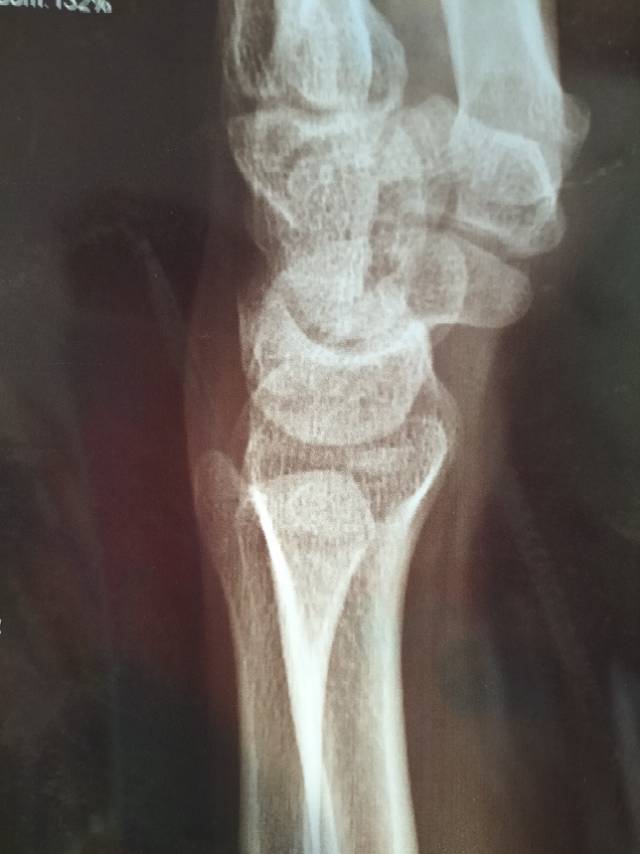

自年底全身骨扫描结果出来后,就想抓紧做腰椎、胸椎核磁,更仔细评估骨转移的进展情况。4号、5号连续两天做完腰椎、胸椎核磁(医院规定不能同一天做),今天上午请骨科医生看了检查结果。因为这位骨科医生之前参与过母亲的骨水泥手术,所以对母亲的情况有些印象,她也很细致地看了骨扫描、CT、核磁的片子,她认为母亲的情况比较稳定,此次骨扫描提示新增的腰1椎棘突转移并不严重,在疼痛不严重的情况下可以不用管,如果疼得严重,可以考虑放疗,棘突不适合做骨水泥等外科手术。医生说从CT片子反映的骨质情况看,经过治疗后是有很大好转的。此外,医生也多指导了几点,我觉得挺有启发:

关于骨扫描报告中提示的两处增生性改变。由于之前没有提示,我问这些增生性改变是否和打了两年护骨针有关?医生说没有关系,对于年纪大的人,骨质增生也比较常见。对于我怀疑增生性改变是否可能也是新的转移,医生说即使是也很轻微,骨转移的发展也没有那么快,轻微的情况下,一般不需要单独对骨头做处理。